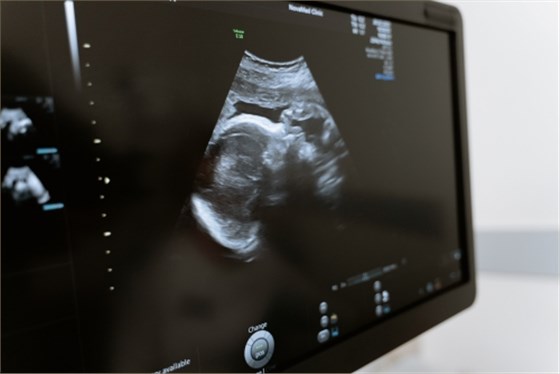

超聲科室主要檢查病變的位置,或者器官、系統(tǒng),比如心臟、甲狀腺、乳腺、血管等,檢查的疾病常見(jiàn)的有甲狀腺結(jié)節(jié)、乳腺結(jié)節(jié)、血管內(nèi)皮瘤、肝臟血管瘤等。